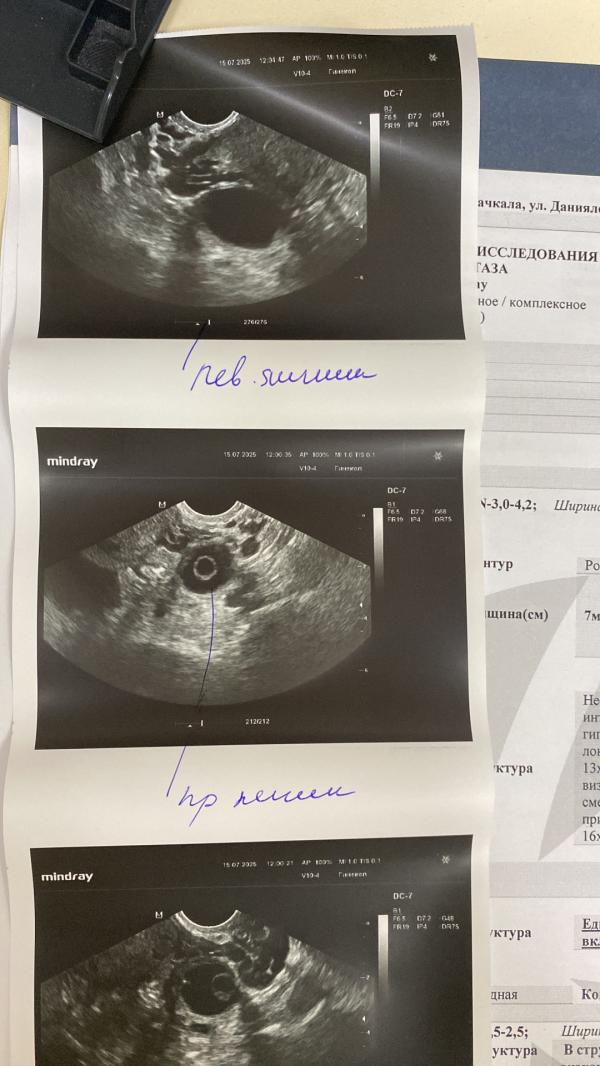

Ох эти экзамены и поступления, которые отражаются на здоровье не только детей, но и их мам ❤️

По итогу нарушения цикла, аномальные маточные кровотечения, кисты… берегите себя ❤️✨